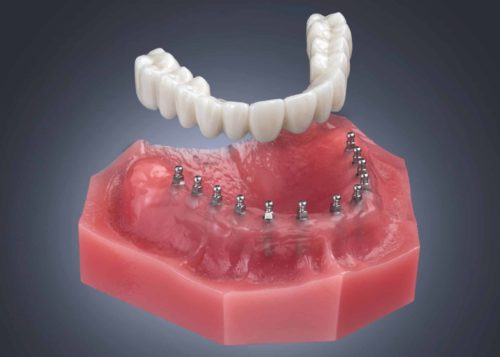

SEMI-REMOVABLE HYBRID RESIN OR ZIRCONIA

HYBRID RESIN OR ZIRCONIA BRIDGE

This is the dental treatment we would provide for our mother-in-law. It is the best alternative to natural teeth!

Involves placement of between 6-10 implants, also determined by bone volume and quality.

This is a fixed hybrid bridge removable by the dentist but not by the patient.

6-10 Mini Dental Implants. Hybrid Bridge removable by the dentist.